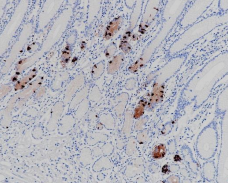

Immunohistochemistry (Formalin/PFA-fixed paraffin-embedded sections) analysis of humann gastric cancer labelling Gastrin with ARB6748.